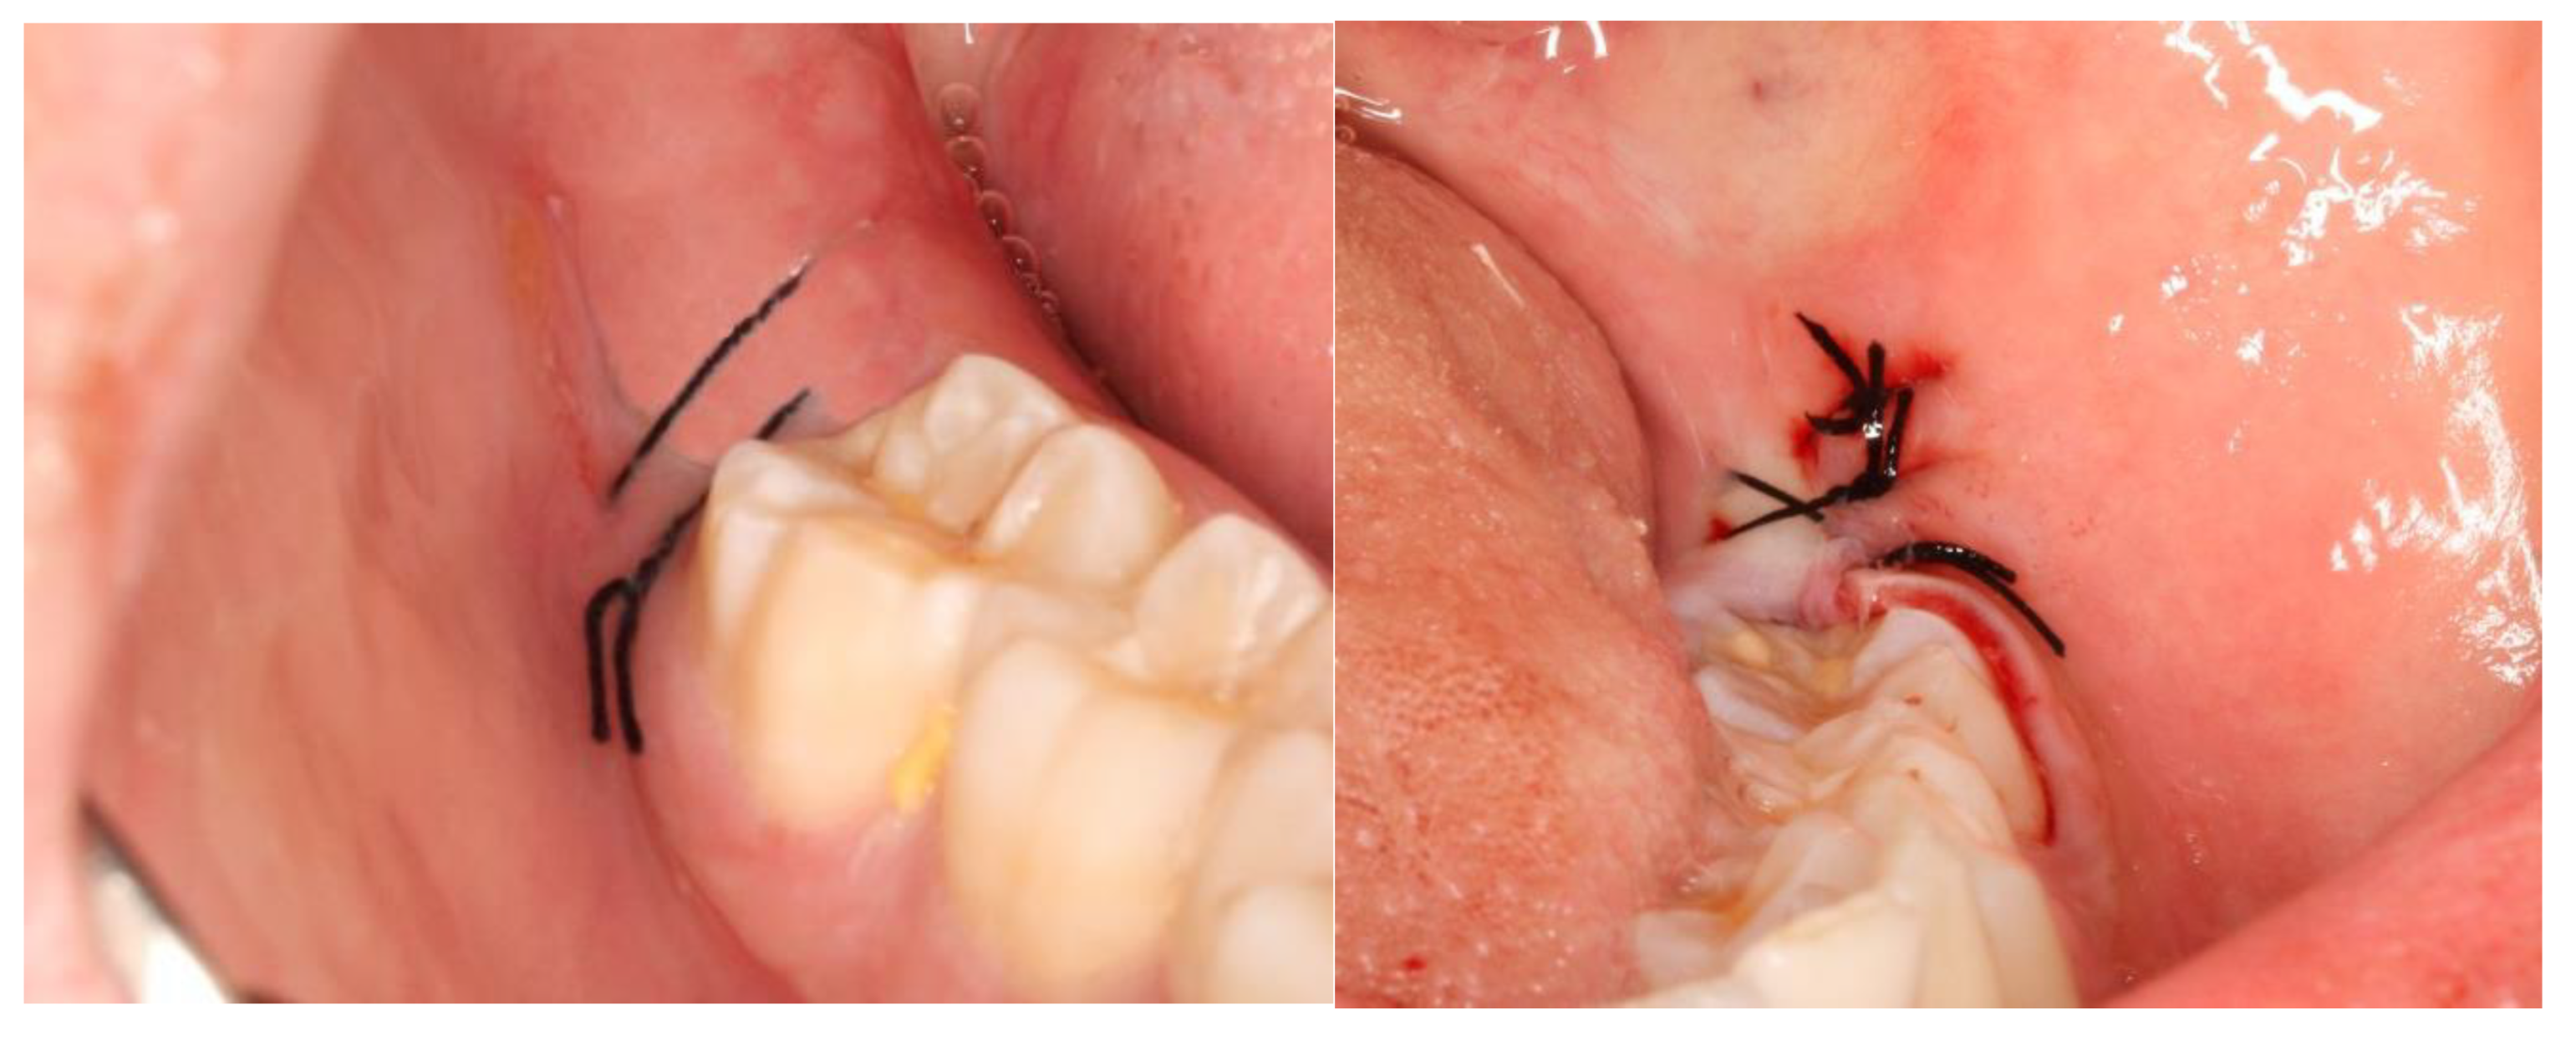

2. Materials and Methods

2.2. Definition of the Variables in Study and Follow-Up of Patients

3. Results